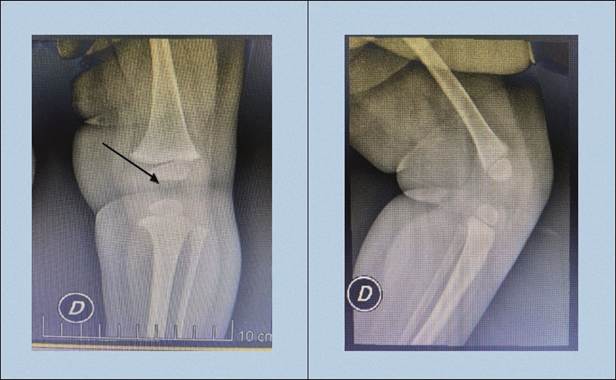

A los 11 meses de vida concurre a control con traumatólogo, se realiza radiografía evolutiva (figura 3) que muestra recuperación satisfactoria. El desarrollo motor es adecuado, al año de vida logró bipedestación normal.

En el presente caso, se realizó tratamiento conservador con la colocación de una férula en las primeras 24 horas de vida. La instauración precoz del tratamiento mejora el pronóstico. Se mantiene la férula cruropédica durante 6 semanas que es el período de tiempo necesario para la cicatrización del tendón cuadricipital elongado. El seguimiento se realiza mediante la exploración clínica, radiografía simple evolutiva y ecografía de cadera de manera de descartar la asociación con la luxación congénita de cadera presente en el 45% de los pacientes con LCR (4,10).

En este caso puntualmente se logró tras el tratamiento médico una flexión de 90° completa y no se encontró asociación con displasia de cadera. La paciente mostró una excelente evolución con una recuperación completa, desarrollo motor adecuado, logrando al año de vida una bipedestación normal.